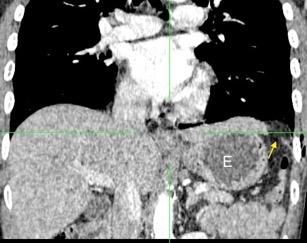

33. ENF. TORACOABDOMINAL. SEUDOQUISTE PANCREÁTICO

3 rasgos: Conexión entre mediastino y lesión pancreática. Derrame pleural Hallazgos de pancreatitis. Matsusue E et al.Three cases of mediastinal pancreatic pseudocysts. Acta Radiol Open. 2016 .